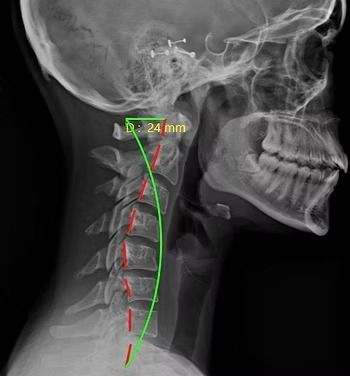

Starting off, we're going to be looking at the side of the neck. With every patient, the first thing we're looking at is the curvature. We're looking at this green curvature line and that's where we ideally want to see the bones of the spine aligned. When we're looking at the red line here next to the green one, that's actually the patient’s alignment right now. You can see that it's straightened out and we don't have as much of that natural curvature that we're looking for in the cervical spine. The second thing we analyze is the amount of space in between the bones or vertebrae. Near the top of the cervical spine, you can see how the spaces are thicker and then when you get down to the lower cervical vertebrae, they're thinner. What is happening here is the disc space is decreasing and that's important to notice because it is the first sign of degeneration in the spine.

Cervical X-Ray patient standing normally, looking straight ahead

With the next patient, you can see a bigger gap between the red and green line. His head is way more forward and the cervical or neck curve is much more straightened out. The significance with that is the more your head is forward, the more force and pressure it's going to not only put on your neck but the rest of your spine as well. Imagine a rubber band that is stretched and stretched and becomes more tight. The other part with posture too is that the further forward the head goes, it actually decreases your ability to breathe and limits a lot of other functions in the body.